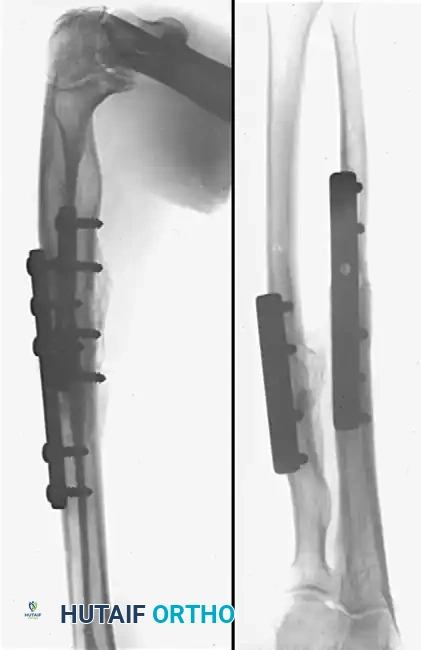

Image

Figure A: Preoperative anteroposterior and lateral radiographs demonstrating a severe malunion of the radial shaft and a hypertrophic nonunion of the ulnar shaft. Note the complete loss of the radial bow and the encroachment upon the interosseous space.